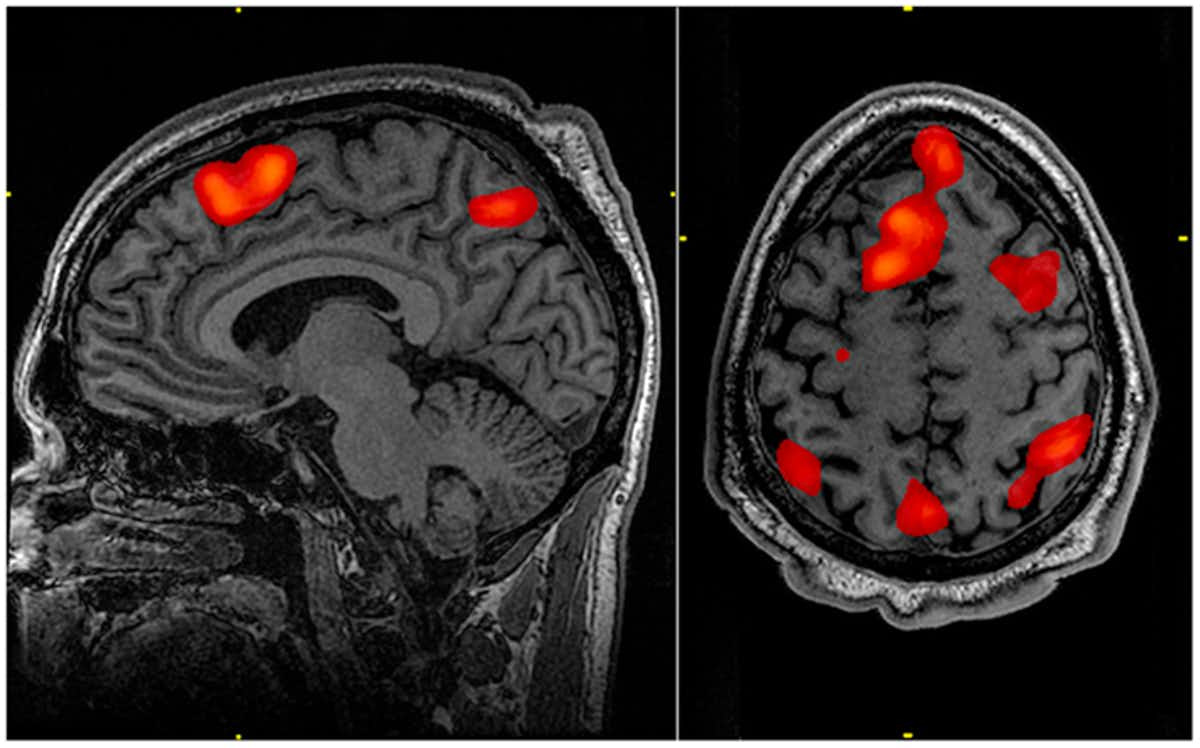

Одним из базовых инструментов нейробиологов является функциональная магнитно-резонансная томография (фМРТ) - это метод исследования, который позволяет измерять нейронную активность головного или спинного мозга. Однако снимки фМРТ чаще всего выглядят довольно скучно, так как они, конечно, показывают, что происходит в мозге, но не могут передать, что при этом чувствует живое существо. И даже сами нейробиологи не испытывают особого восторга от такого подхода.